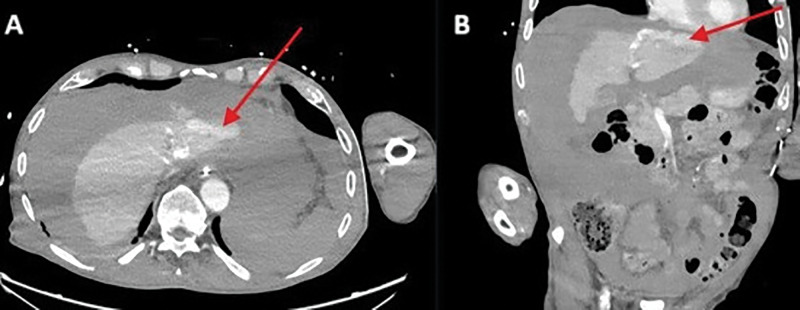

Teaching point: Laceration of the left hepatic vein is a rare but potentially fatal complication of cardiopulmonary resuscitation (CPR) and should be considered in patients with unexplained hemodynamic instability following resuscitation.

Abstract Image